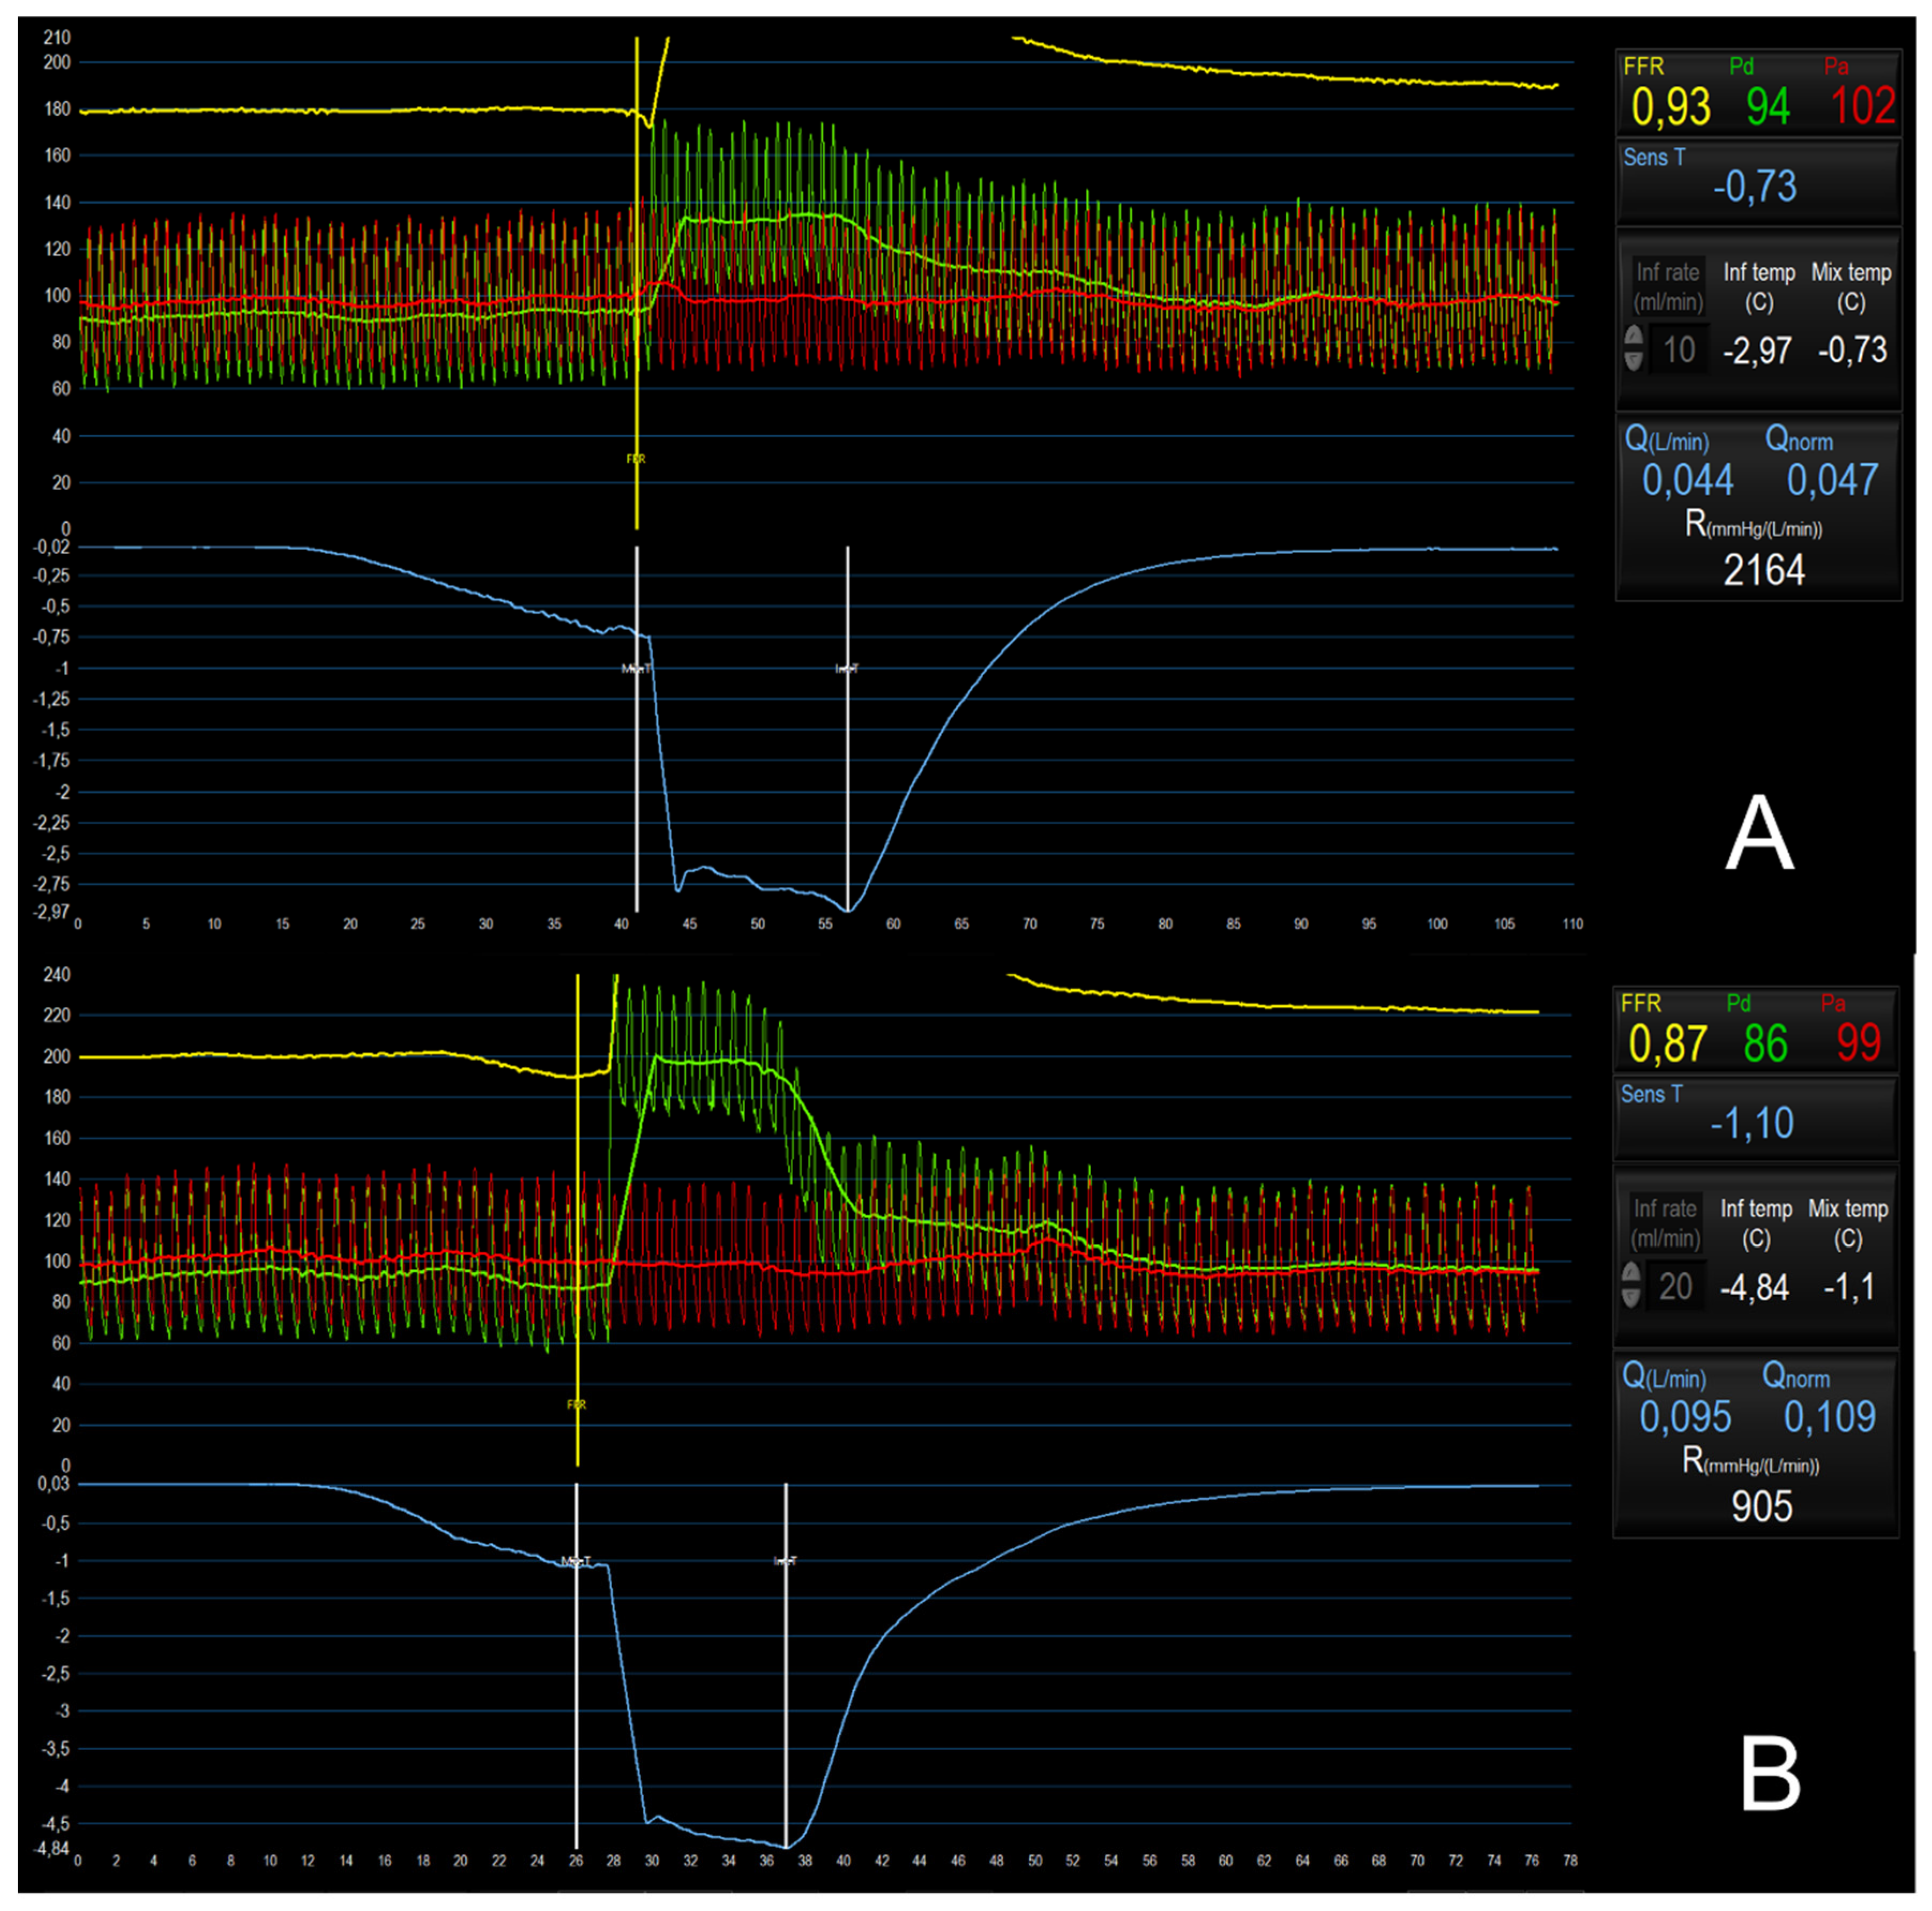

Figure 5. microvascular assessment with the continuous thermodilution method. Panel A: bolus thermodilution assessment during saline infusion reproducing resting conditions (10 ml/min). Panel B: bolus thermodilution assessment during saline infusion reproducing hyperemia (20 ml/min) showing low values of Q (95 ml/min) and high value of R (905 UW) suggestive of coronary microvascular dysfunction.

Absolute coronary flow (Q) is calculated as the ratio of Ti to T, multiplied by the saline infusion rate (Qi) and corrected for a constant related to the difference between heat and density of blood and saline. Absolute microvascular resistance (R) is calculated as the ratio between the distal coronary pressure Pd and Q (Table 1) [67]. Notably, the repetition of these measurements under rest and stress conditions allows the calculation of both CFR and of a novel index, the microvascular resistance reserve (MRR), which is obtained by the ratio between rest and hyperemic Q with a compensation for changes in blood pressure during hyperemic conditions and the presence of epicardial disease (Table 1). MRR is then the ratio of true resting microvascular resistance (Rµ,rest) as it would be in the hypothetical case that the epicardial artery would be completely normal, and hyperemic microvascular resistance ( Rµ,hyp) and expresses the capacity of the microvasculature to decrease its resistance under stress conditions [5,58]. Currently, the clinical application of Q, R and MRR is limited by the lack of validated cutoffs. However, recent studies have addressed the issue and proposed normality values. In a recent study assessing the relationship between CFR/IMR and Q and R, Konst et al. proposed normality cutoff for Q and R respectively of 320 ml/min and 487 WU [68], while another study by de Vos et al. suggested that MRR values >2.7 and <2.1 respectively exclude and confirm the presence of CMD [69]. Despite its clinical application is still limited by its relatively recent introduction, the continuous thermodilution method has been validated against the gold standard positron emission tomography (PET), showing a strong correlation and agreement between PET- and invasive-derived CFR [70]. In addition, it has proved to be safe and highly reproducible [67]. Figure 5 provides an exemplificatory case of CMD assessment with the continuous thermodilution method.